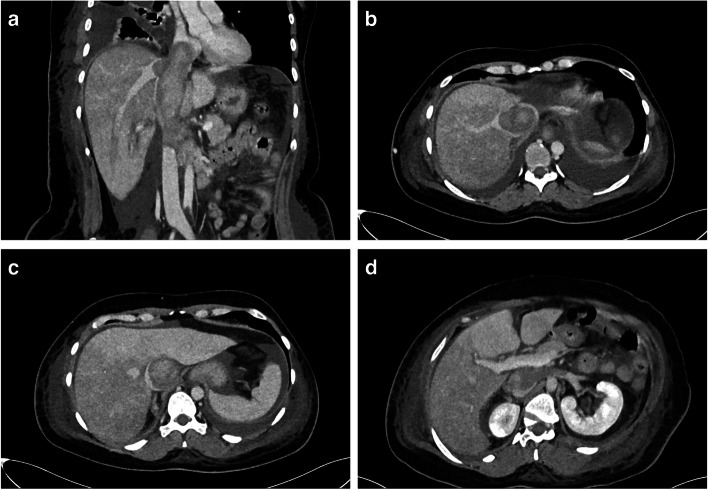

Case presentation: A 44-year-old female presented with fulminant liver failure secondary to inferior vena cava (IVC) thrombosis. Contrast-enhanced computed tomography subsequently revealed a thrombus within the IVC, extending cranially to the right atrium and caudally to the renal veins. The patient's condition, characterized by early comatose symptoms, necessitated surgical intervention. Under extracorporeal circulation, a right atriotomy with thrombus lesion removal and descending thrombectomy of the IVC was performed. Hepatic congestion resolved after the thrombus was removed. A pathological examination of the excised thrombus revealed the presence of high-grade leiomyosarcoma.